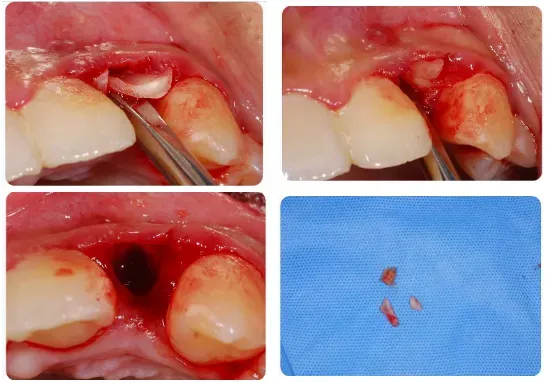

6、复杂的多根牙也可以“简单”拔除;

●通过微创方法解决复杂的单根牙、多根牙

小断根处理的新思路和注意事项